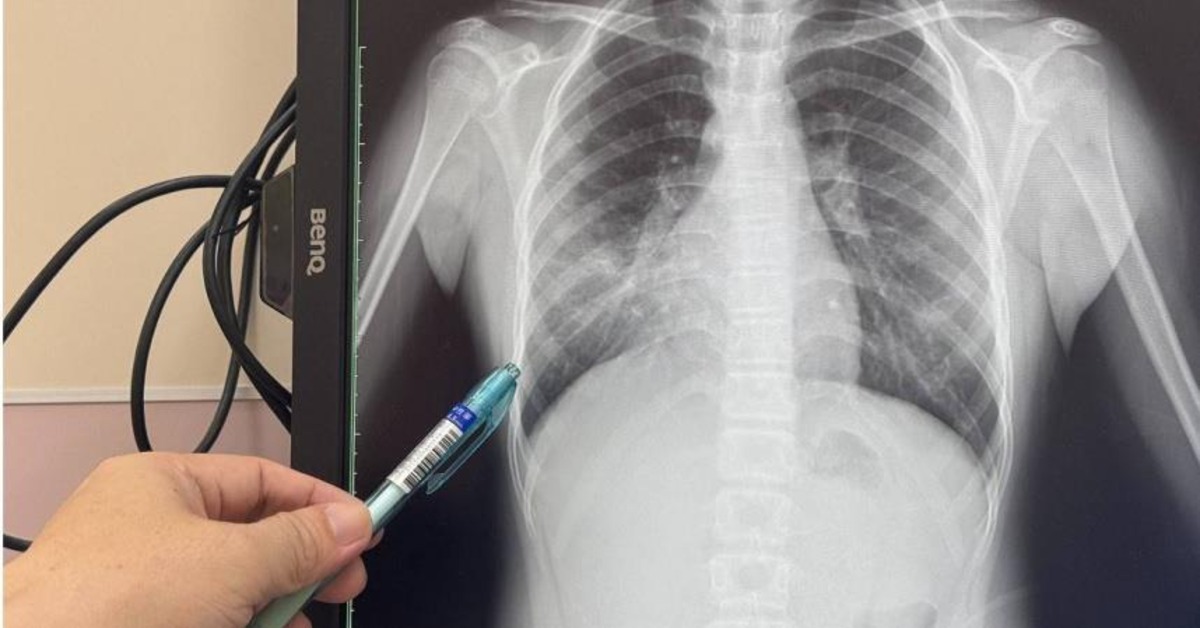

大甲李綜合醫院小兒科主任醫師余秋霖表示,近日門診中不少前來就診的孩童,咳嗽至少都逾一個禮拜,不少家長先把孩子帶到診所看診,但是就醫、吃藥皆沒有辦法治癒,甚至還愈來愈嚴重,轉而到醫院就診,經過詳細檢查、篩檢,確認感染黴漿菌肺炎,X光還呈現大片反白,證實罹患「會走路的肺炎」。

余秋霖指出,門診中罹患黴漿菌肺炎的孩童皆就讀國小以上,也有就讀國中的少年,其中,一名8歲的孩童家中沒人患病,進一步追問得知「班上的同學也咳嗽不停」,研判是遭到班上同學的感染。由於黴漿菌肺炎主要由飛沫、接觸傳染,傳染力極強,在學校、家庭中如果有人罹患黴漿菌肺炎,沒有緊戴口罩,便很容易遭受傳染。